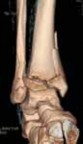

TRIPLANE FRACTURES: SALTER-HARRIS TYPE IV FRACTURES

1. Triplane fractures are typically geometrically complicated fractures that, as mentioned above, are transitional fractures that involve the distal tibial physis at the time of its asymmetric closure during the early teenage years.

2. Because these fractures are typically quite complex, we advocate CT scans with three-dimensional reconstruction for visualization and surgical planning (see Fig 2).

27. The surgical approach depends on the complexity of the fracture: these fractures can be two-, three-, or four-part fractures (

TECH FIG 5A–C

).

28. Growth plate disturbance is not typically a problem owing to the proximity to skeletal maturity in these patients.

29. Anatomic alignment of the articular fracture at the joint surface is important in the outcomes of these patients.

A B CTECH FIG 5•

Triplane fractures can be two-part (

A

), three-part (

B

), or four-part (

C

) fractures, but all involve an intra-articular epiphyseal component in addition to a metaphyseal component, making them Salter-Harris type IV fractures.

(continued)

--- DTECH FIG 5 •

D,E. In complex triplane fractures, screws often need to be placed both at the level of the epiphysis and the metaphysis, as dictated by the specificE fracture pattern. 1. Two-part and sometimes three-part fractures can be ■ The medial incision allows application of the epiphy-anatomically reduced and fixed through an isolated an- seal screw.

terolateral approach. ■ Both incisions will allow direct visualization of the

2. Generally lag screws need to be placed at the level of both fracture reduction.

the epiphysis and metaphysis, and it is often most practi- ■ If the fibula is significantly fractured and shortened it is cal to employ a two-incision approach to obtain reduction important to either anatomically reduce or reduce and and better access to fracture fixation (

TECH FIG 5D

). internally fix the fibula to obtain an appropriate tem-

1. The anterior incision is used to obtain lag fixation of plate for the anatomic length of the ankle mortise. the metaphyseal fragment, often in the coronal

plane, and to visualize the joint surface.